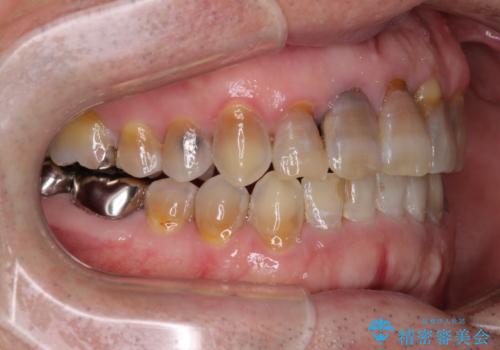

上顎の狭窄歯列 インビザラインによる拡大矯正

- 前歯の叢生と臼歯のクロスバイトを気にして来院された患者様です。

急速拡大装置による上顎の側方拡大を行い、その後はインビザラインより歯列を改善することとしました。

20代後半以降の男性は上顎骨の側方拡大処置の成功率が低く、今回も骨を拡大することができませんでした。

しかしながら、歯列を側方に拡大することができ、その後はインビザラインにて叢生を解消することができました。